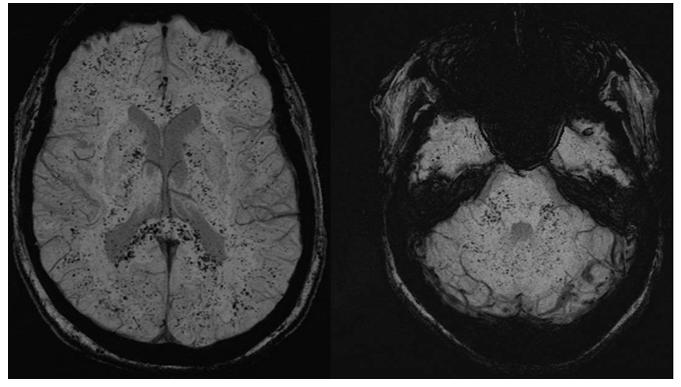

DIC SWI示双侧大脑半球、小脑及脑干弥漫性CMBs

轻度创伤性颅脑损伤 SWI示近皮层、眶额和颞叶多发CMBs。

脂肪栓塞综合征通常由长骨骨折引发,骨髓中游离的脂肪进入血液循环所致。在脂肪栓塞综合征患者中,CMBs常见且主要分布在白质(尤其是分水岭区),也可见于灰质。这些脂肪栓塞相关CMBs与DWI上小的梗死相关。

脂肪栓塞综合征 骨折3周后SWI示双侧皮层下和脑室周白质、大脑半球、大脑脚、胼胝体后部弥漫性的CMBs (A-D)。骨折5周后复查SWI同前(E-F)。